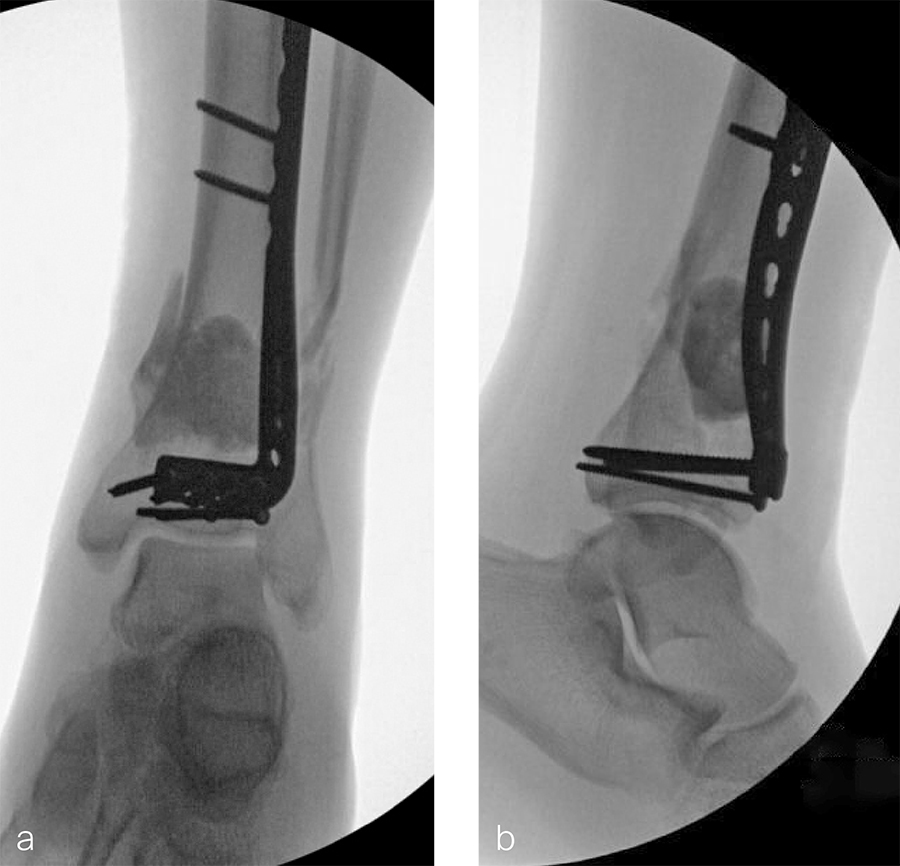

A 59-year-old man working for the city of Tulsa suffered an open distal tibia plafond fracture on the left leg when he fell into a sewer hole with raw sewage (Fig 1). The wound was grossly contaminated, and he was taken immediately to the operating room (OR) for incision and drainage and application of a spanning external fixator. Bone loss was noted anterior and medial (about 2.5 or 3 cm) but only about 2025% of the bone circumference.

After repeated incision and drainage, 2 days later the fracture was repaired with an anterior lateral tibial plafond plate (Fig 2). Vancomycin and tobramycin impregnated antibiotic beads were placed in the bone defect.

The patient was discharged on hospital day 6 to a rehabilitation facility with his left lower extremity in a splint and touch down weight bear allowance. He returned 2 weeks later with drainage from the medial traumatic wound. In addition, he had a gastrointestinal bleed from use of nonsteroidal antiinflammatory drugs. Once the gastrointestinal bleed was stabilized, he was taken the next day to the OR for another incision and drainage. Further, more significant, devitalized bone was resected, and an antibiotic cement spacer was placed (Fig 3). Deep culture samples were taken despite knowing the antibiotic resorbable beads had been placed in the wound at the time of initial closure. The plate was left in place, but a planned exchange plate/nailing was to be performed pending final culture results.